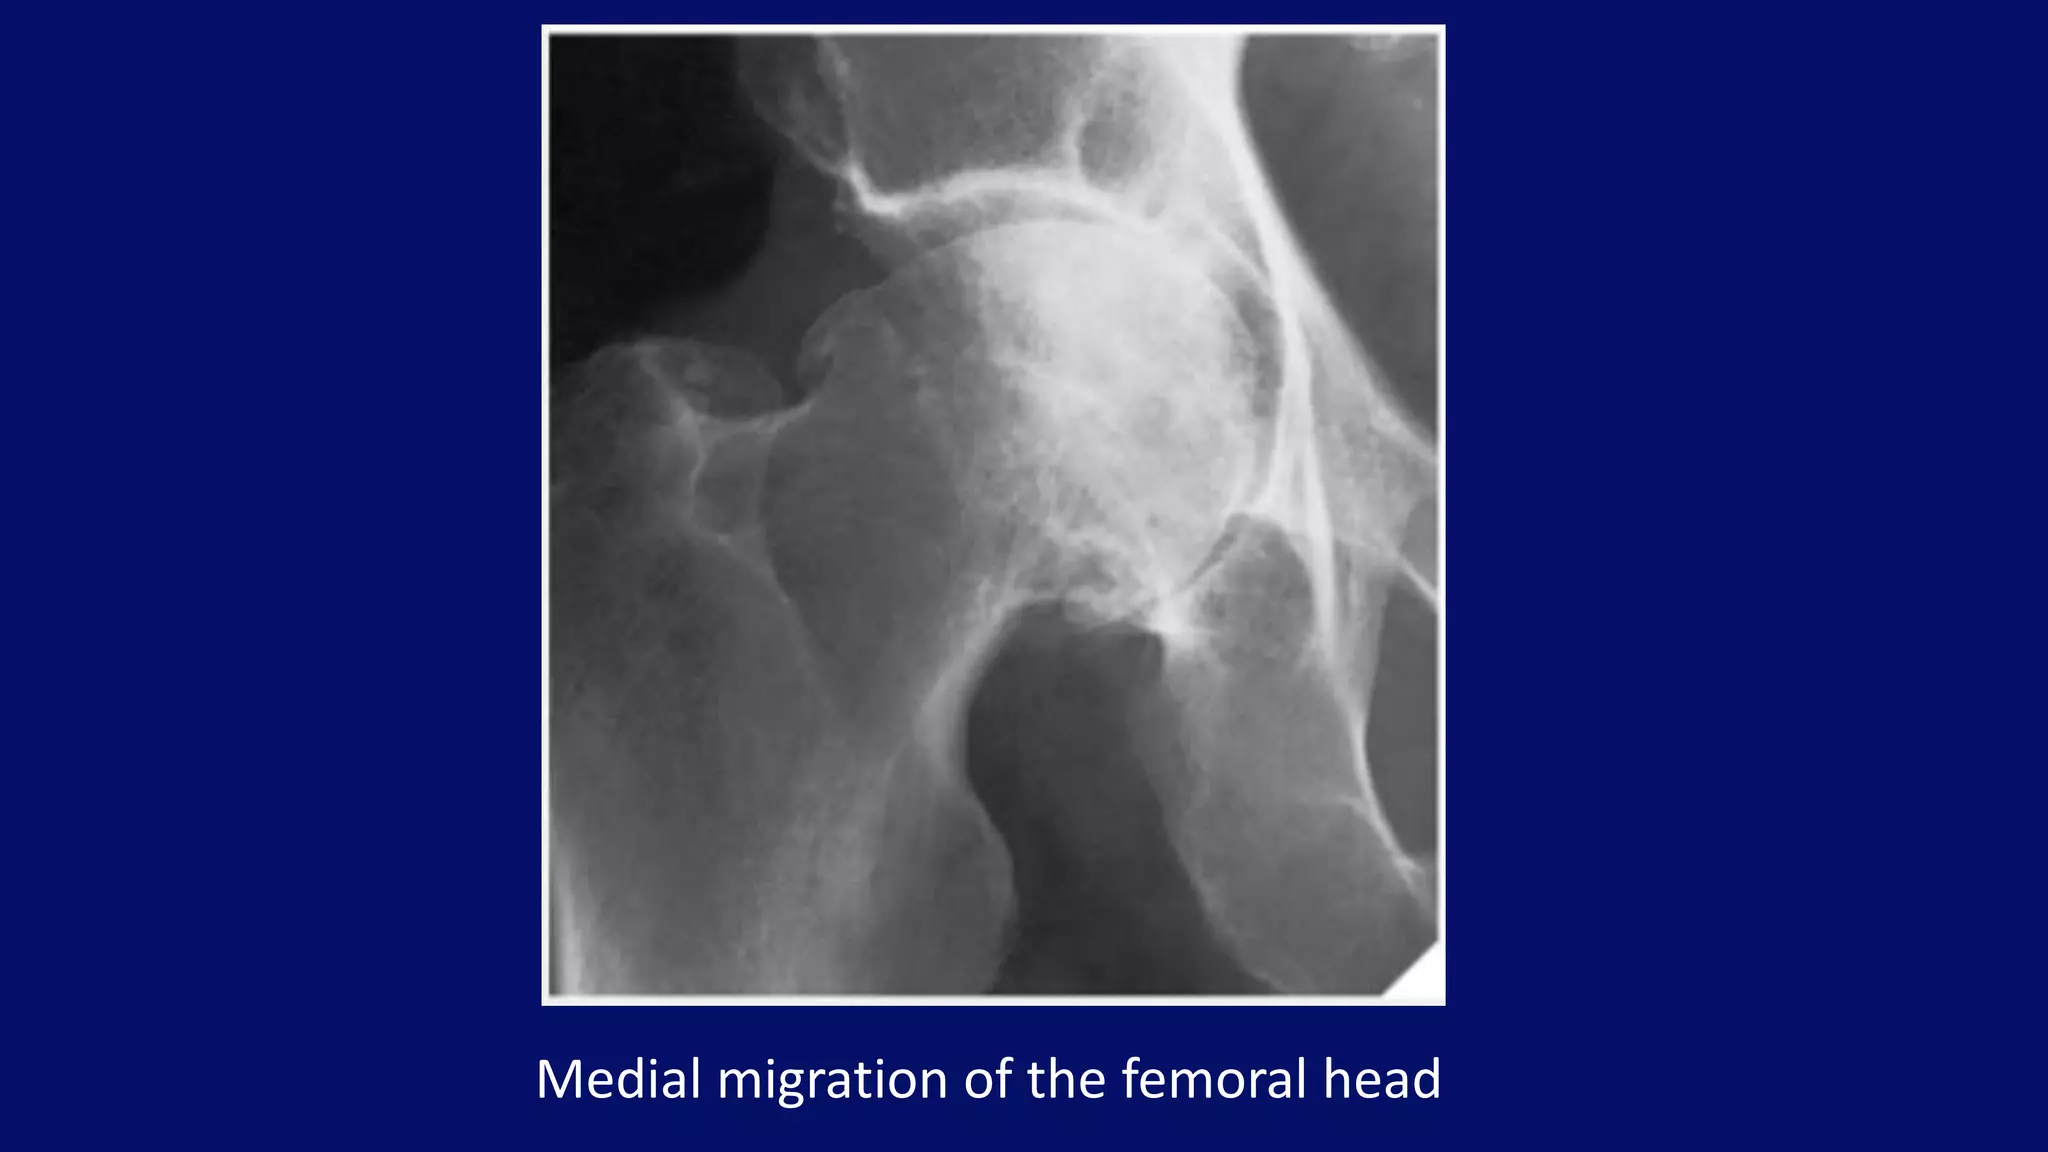

Medial migration of the femoral head

Postel coxarthropathy

(aka rapidly destructive arthrosis)

• occurs predominantly in women

• characterized by rapid chondrolysis

• no/very little reparative changes

• mimics Charcot joint or infectious arthritis

Right hip Postel Coxarthropathy